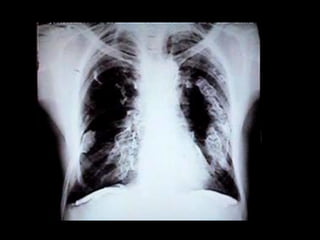

Calcificación metastásica en el pulmón por

METASTÁSICA: Es la quese produce en individuos con una hipercalcemia de base. 1. Esta hipercalcemia está producida por hiperparatiroidismo, aumento de la vitamina D o destrucciones importantes de tejido óseo por metástasis óseas. 2. Los órganos que se afectan son principalmente el riñón, el estómago, los pulmones y los vasos.

Calcificación metastásica enel pulmón por hipercalcemia